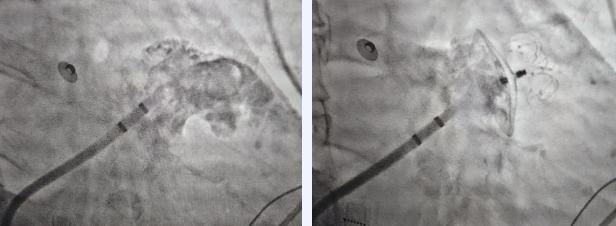

经过仔细讨论手术方案,在家属的期待下,房颤一站式手术紧锣密鼓的开始了。术中,治疗团队先用造影技术让冠状静脉显影,精准定位隐匿在心脏血管网络中的“罪魁祸首”——Marshall静脉,用球囊封堵静脉开口,精准灌注无水酒精,让这一片心肌区域失去电传导能力,从而切断房颤的“火种”。

团队使用消融导管,对心脏内膜的关键部位进行精细消融,彻底阻断异常信号的传播。

随后,他们在患者左心耳处植入封堵器,“封死”了这个最容易形成血栓、诱发卒中的区域,从源头上降低中风风险。